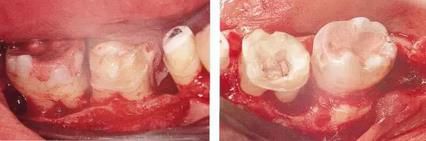

360截圖20170422102030273.jpg

▲圖11-3,4

▲圖11-3,4 齦瓣剝離翻開(kāi)的狀態(tài)。右下6的遠(yuǎn)中牙根有較深的骨組織缺失,右下7的頰側(cè)有II度根分叉病變和近遠(yuǎn)中側(cè)有垂直型骨組織缺失。